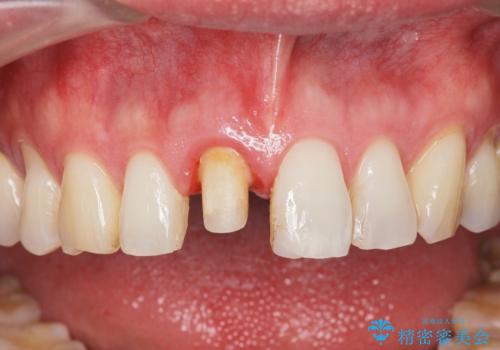

感染の疑われる根管内に対し再度根管治療を行い、セラミッククラウンを作製することで審美性の回復します。

- 13.2万円(ジルコニアクラウン・仮歯)費用は治療当時の料金となります